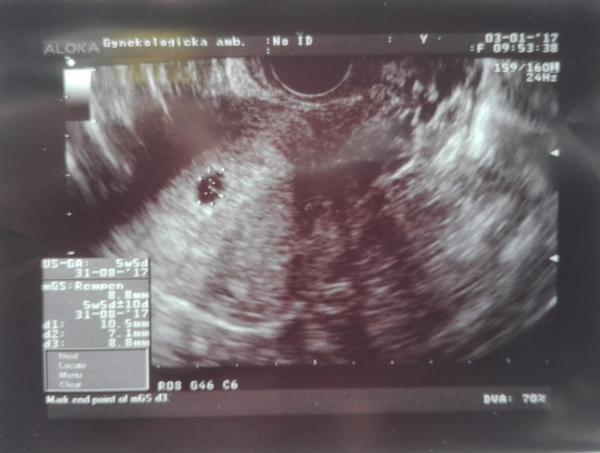

Náš duch na teste je nádherná fazulka. ☺ Drobček 5tt+5d ☺